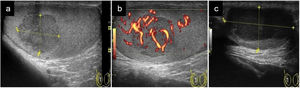

Ecográficamente se caracteriza por aumento de flujo en el Doppler color. Suele ser unilateral. El epidídimo puede estar aumentado de tamaño y ser heterogéneo (vídeo 3). Puede existir hidrocele reactivo y engrosamiento de las cubiertas escrotales. Habitualmente comienza afectando a la cola del epidídimo y se extiende al cuerpo y a la cabeza y si la infección progresa también al testículo (orquioepididimitis). En la orquitis el testículo puede presentar una ecogenicidad heterogénea y hay un aumento del flujo en el Doppler-color en el testículo afecto, al compararlo con el contralateral1,14,28,29 (Fig. 7).

a) Epididimitis con engrosamiento e hipoecogenicidad del epidídimo (señalado con flechas y medido su grosor entre cruces); b) Orquitis avanzada con zonas de marcada hipoecogenicidad del parénquima testicular y área periférica abscesificada con captación Doppler; c) Evolución de «b» una semana después con área abscesificada en polo inferior testicular con hidrocele tabicado secundario (señalado con flechas).